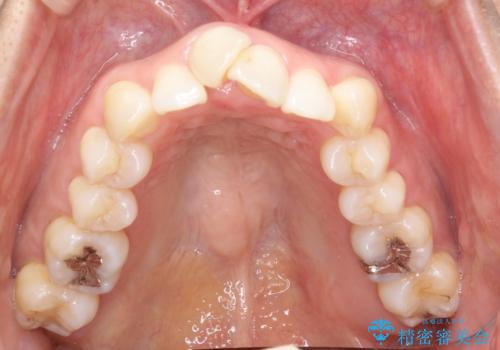

重度のガタガタのインビザラインによる非抜歯矯正

- 上下の歯のガタガタを主訴に来院されました。

インビザラインで奥歯を後方に移動させるのと、歯と歯の間をわずかに削ることでスペースを作り、歯を並べる計画としました。